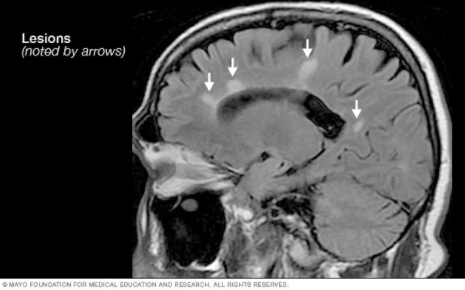

MRI

MRI is a diagnostic radiological exam. It is often used in the diagnosis of MS. The exam can be down with or without contrast. Contrast is an Intravenous agent used to highlight the lesions or area of interest. The contrast typically used in MR is gadolinium.

Findings consistent with MS are usually high signal white matter lesions in the brain and spinal cord.